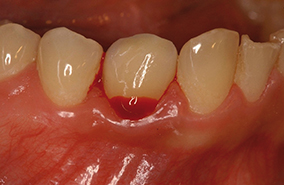

Légendes des 8 photographies :

1 - Mucosite : saignement au sondage révélant une inflammation de la muqueuse péri-implantaire sans perte osseuse.